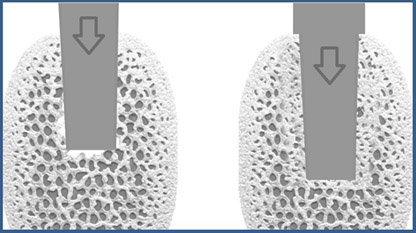

Bone Condensing: ein konisches Instrument wird vertikal so in den Knochen eingebracht, das sich die Kavernen im Knochen verdichten. Es entsteht Knochen mit kleineren Hohlräumen (rechts)

Bei Vorliegen von weichem, weniger dichtem Knochen wird zunächst nur ein kleines Loch gebohrt und das Implantat vorsichtig eingeklopft. Der Vorteil: Es wird weniger Knochenmaterial abgetragen. Der Knochen bleibt erhalten und wird verdichtet. Dieses Verfahren kann dem Implantat einen besseren Halt geben. Zusätzlich ist die Einhaltung einer längeren Einheilungszeit zu empfehlen (6 – 12 Monate im Oberkiefer).